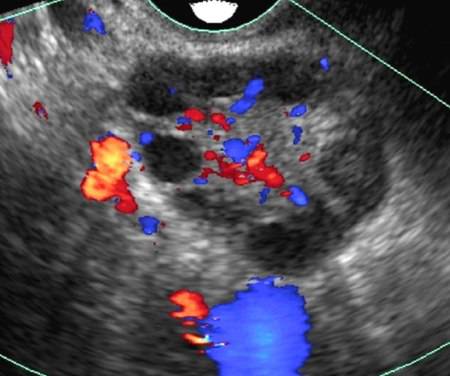

Фото УЗИ при серозной папиллярной цистаденоме